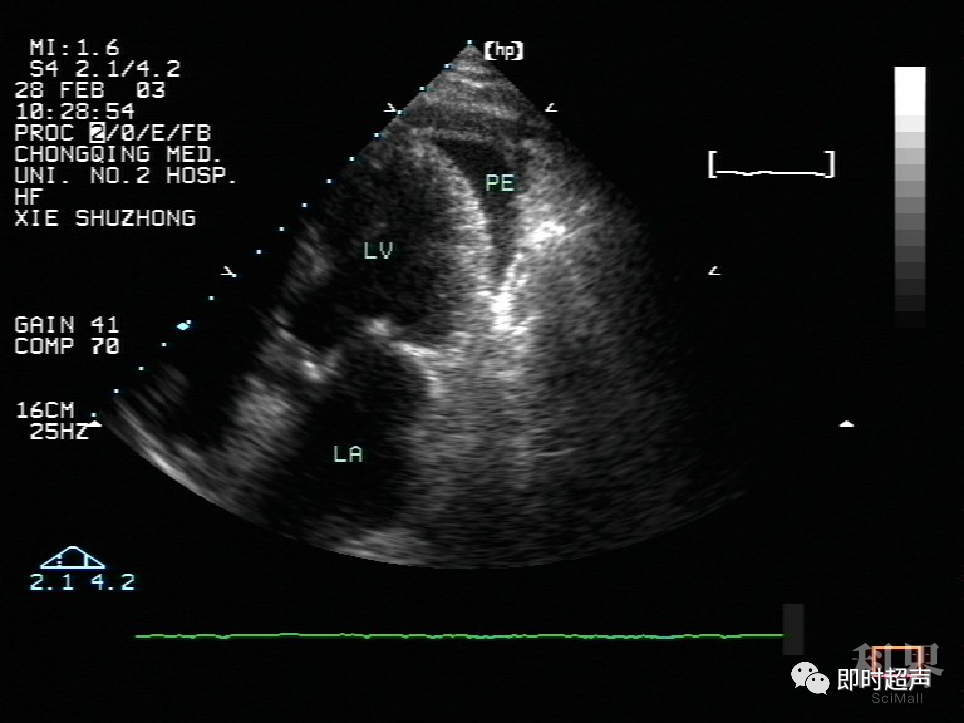

【鉴别】心包积液的超声诊断及鉴别